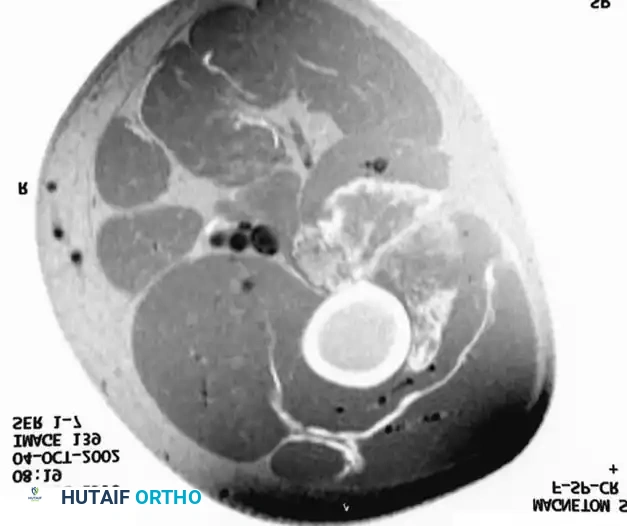

Figure 2: Axial MRI of the same patient following a full course of preoperative radiation therapy. Note the dramatic decrease in the size of the mass and the increased definition of the surrounding tissue planes. This radiologic response makes the subsequent wide resection technically much easier and oncologically safer.